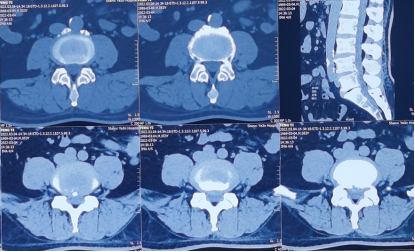

术前影像学资料

内镜下成功取出突出的椎间盘